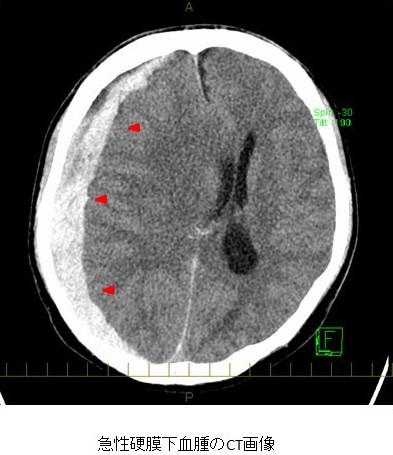

頭部外傷が原因で、脳の表面(くも膜)と硬膜との間に貯留した血腫のことを指します。頭部打撲による脳挫傷や脳表の血管損傷、回転加速度による頭部外傷では架橋静脈の損傷によって生じることがあります。受傷直後から意識障害や運動麻痺を呈している場合もあれば、当初は意識レベルが比較的良くても血腫増大によって神経症状が急速に悪化する場合もあります。特にスポーツに伴う急性硬膜下血腫では脳挫傷を伴わないことが多く、外傷直後に意識障害を認めず、数時間以内に症状が進行することもあり、注意が必要です。衝撃を受けた頭部と反対側に血腫を認めることもあります。診断にはCTによる画像診断が行われ、頭蓋骨と脳の間の三日月状の高吸収域が特徴的です。急性硬膜下血腫は、脳挫傷やびまん性脳損傷などの重篤な脳損傷を合併していることが多いため、著明な脳浮腫が進行し頭蓋内圧亢進(頭蓋内圧の上昇)も認めることがあります。